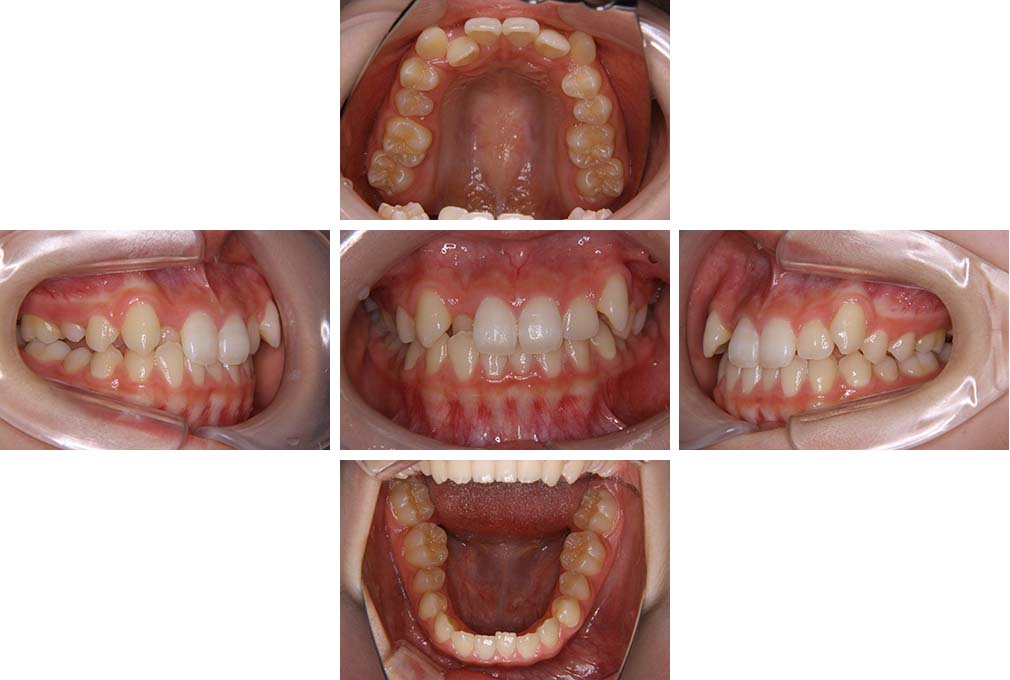

CASE:02

下顎前歯部叢生、小臼歯4歯先天欠損

初診時年齢 14歳3か月

性別 女性

治療費の目安 70万円(治療開始時)

上顎左右側小臼歯3歯、下顎左側第二小臼歯の先天欠損と下顎前歯の叢生を主訴として近隣一般歯科から紹介来院した。

上顎左側第一、第二小臼歯、右側第一小臼歯、下顎左側第二小臼歯が先天欠損であったが、左上第二乳臼歯の根の吸収がほぼ無いことから、これを残すこととして、下顎左側乳臼歯と、右側第二小臼歯を抜歯していただきマルチブラケット装置を使用して動的治療を行った。矯正用ゴムなどの協力状態も良く2年0カ月(調整来院19回)で装置を撤去し保定へ移行した。動的治療終了13年2カ月での来院時には下顎左右側智歯が萌出していたが、垂直的に萌出していたため抜歯は行っていない。

治療前

14歳3か月

治療後

動的治療期間2年0カ月

16歳7か月

13年経過

動的治療終了後13年2カ月

30歳0か月